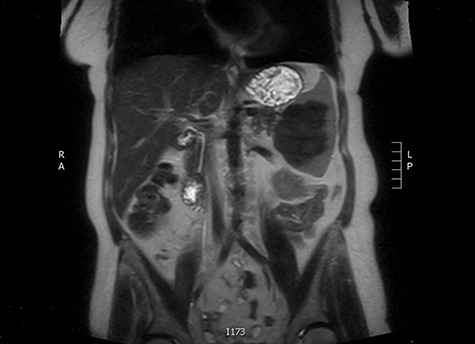

The latter was discussed in the lung multi-disciplinary team (MDT) meeting. They concluded that the pleural mass was most likely due to post-inflammatory changes. In absence of concerning features, further monitoring or intervention was deemed unnecessary. The splenic mass was then discussed in the hepatobiliary MDT meeting. They recommended obtaining tissue biopsy to aid diagnosis. However, it only showed fibrotic tissue with possible granulomas. The indeterminate histology prompted a repeat CT scan and further magnetic resonance imaging (MRI) to assess the mass further and exclude the possibility of lymphoma. These scans showed stable appearance of the splenic lesion at 6 cm (Figs 1 and 2). The CT scan also picked up numerous small calcifications scattered throughout the peritoneal cavity.